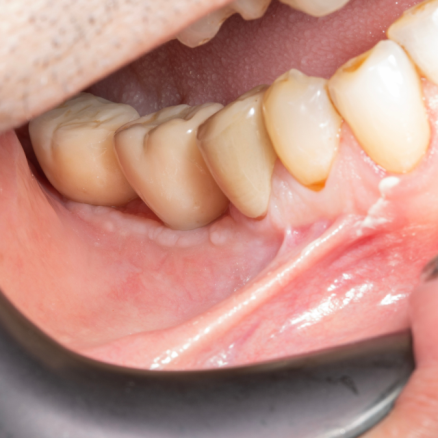

İmplant etrafındaki kemik açıklığını kemik grefti ile tedavi ettiğimiz vakamız